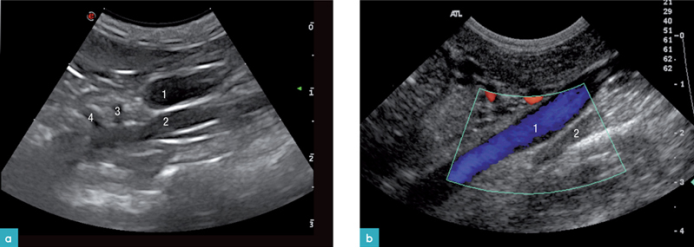

使用右侧卧位和仰卧位结合检查左侧肾上腺。先找到左肾的头极,然后向内侧移动,找到左肾动脉与腹主动脉的平面。

左侧肾上腺位于肠系膜前动脉根部的后方(图1a)。左侧膈腹腔静脉位于左肾上腺的腹侧。

检查右侧肾上腺,采用仰卧位结合侧卧位,探头放置在肋弓下。以后腔静脉作为解剖参照物,右侧肾上腺位于右肾的头侧,后腔静脉的背外侧。在很多情况下,膈腹部静脉位用于定位右侧肾上腺。

猫的肾上腺通常和身体的矢状面有轻微的交叉,尾极更靠中线,头极较尾极更靠外侧。因此,如果在身体的矢状面上观察肾上腺,它会呈椭圆形;如果在肾上腺自身的矢状面上观察,腺体则呈双叶状。(图2.视频1-3)

肾上腺由起源于主动脉的动脉(腹腔动脉、肾动脉、膈腹部动脉、腰动脉) 供应血液。通过膈腹部静脉引流静脉血。